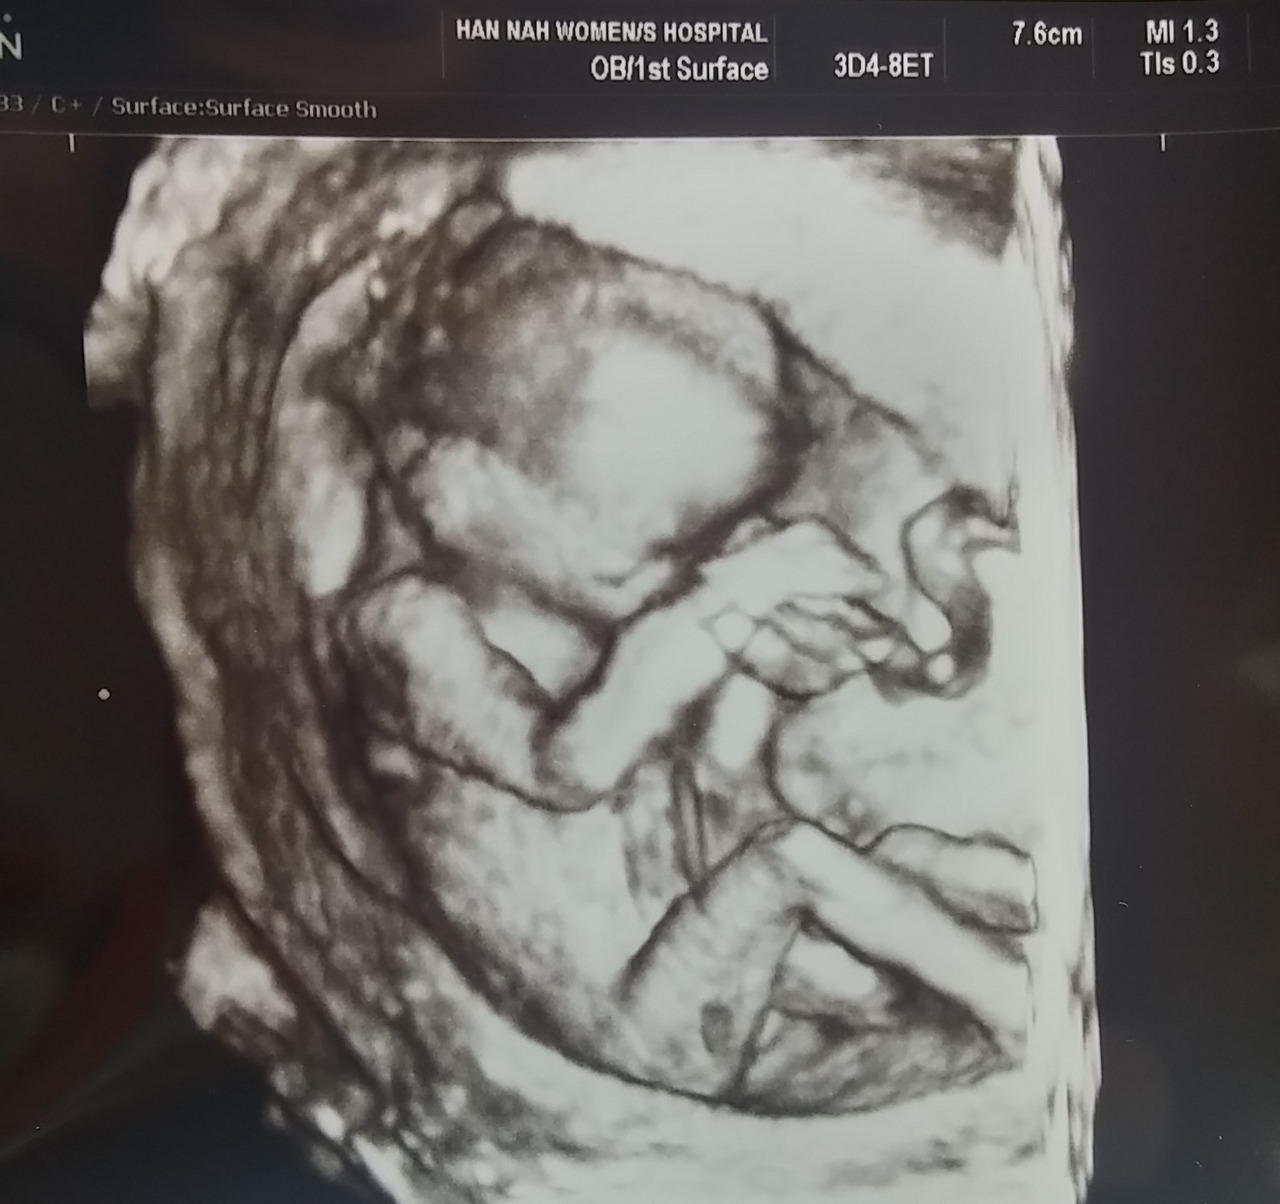

-아이의 사진을 봤을 때, 어떤 감정이었어?

ㄱ: 정말 한 인간이 내 뱃속에 있어서 신기했지. 실제로 보질 못하니 사진만으로는 크게 와 닿은 감정은 없었어. 그저 빨리 실제로 보고 싶다 어떻게 생겼을지 너무 궁금한 마음이었어.

: 나도 비슷했어. 그거 신기한 마음뿐이었던 것 같아. 막 감동받고 그런 건 없었어.